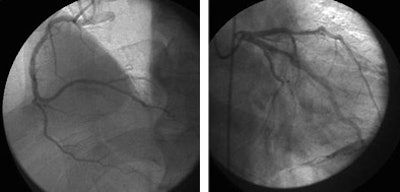

![]() |

| A 59-year-old man presented with classic chest pain symptoms to the ER five days earlier. He was asymptomatic upon presentation to the practice, but opted for an office-based CTA rather than wait three weeks to see a cardiologist. Images top to bottom: Right coronary artery stenosis (arrows) shown on 64-slice CTA at left, cardiac catheterization at right. Next, a normal left circumflex artery (arrows) is depicted on 64-slice CTA at left, cardiac catheterization at right. Next two image sets: Left anterior descending artery stenosis (arrows) is seen on 64-slice CTA at left, cardiac catheterization at right. Bottom image shows excellent outcome on cardiac cath following stenting. |